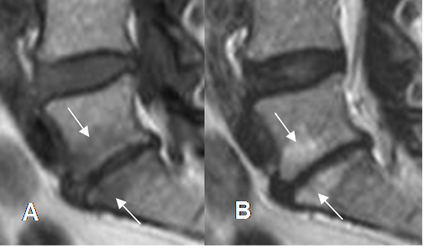

Fig 141 B. Diferencial de espondilodisquitis.

A: RM sagital en T1, B: RM sagital en T2 y C: RM sagital en STIR. Cambios inflamatorios en las placas terminales de L5-S1, Las cuales son hipointensas en T1 e hiperintensas en T2 y STIR. (Flechas).